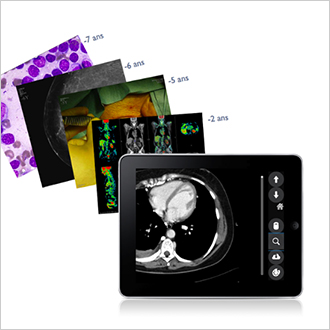

TM-MACS

Le système MACS (Multimedia Archiving and Communication System) a pour objectif de soutenir la tendance à la numérisation des activités et des services cliniques. Cette solution multimédia s'étend à tous les autres services cliniques (ophtalmologie, dermatologie, cardiologie, bloc opératoire, service des urgences, anatomie pathologique, etc.). Telemis prend en charge tous les formats d'images, qu'ils soient au format DICOM ou non. Les cliniciens ont accès aux images et aux vidéos contenues dans les dossiers des patients, qu’ils peuvent consulter à des fins diagnostiques. Des outils d’analyse et d’affichage (zoom, loupe, annotations, mesure de distance, etc.) sont disponibles afin d’améliorer le diagnostic. L’utilisation d’étiquettes permet de créer des groupes d’examens et d’y accéder en un seul clic. Un système de recherche personnalisé permet de trouver très rapidement le dossier patient ou l’examen souhaité.